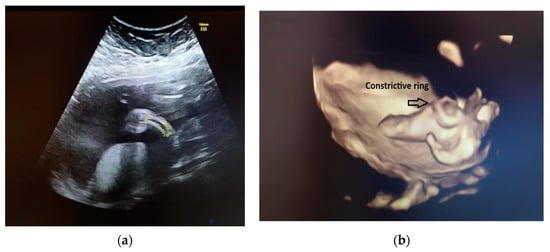

We explained to the parents that this anomaly was isolated. Because of the unilaterality of the defect, it was less likely that this was associated with underlying chromosomal abnormalities or genetic syndromes. The amniocentesis results showed a normal karyotype and normal array CGH. Our diagnosis was amniotic band syndrome. This is a rare finding when a fibrous amniotic band entangles parts of the fetus and constrict the blood supply to a specific part and causes the deformity of different parts of the fetus (see Figure 2).

Figure 2. Visualization of the constricted area of the right shin.